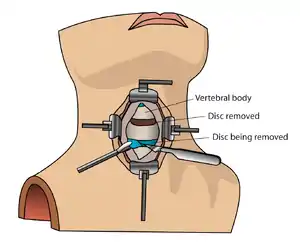

There are many types of spinal fusion techniques. Each technique varies depending on the level of the spine and the location of the compressed spinal cord/nerves.[4] After the spine is decompressed, bone graft or artificial bone substitute is packed between the vertebrae to help them heal together.[2] In general, fusions are done either on the anterior (stomach), posterior (back), or both sides of the spine.[4] Today, most fusions are supplemented with hardware (screws, plates, rods) because they have been shown to have higher union rates than non-instrumented fusions.[4] Minimally invasive techniques are also becoming more popular.[13] These techniques use advanced image guidance systems to insert rods/screws into the spine through smaller incisions, allowing for less muscle damage, blood loss, infections, pain, and length of stay in the hospital.[13] The following list gives examples of common types of fusion techniques performed at each level of the spine:

Cervical spine

- Anterior cervical discectomy and fusion (ACDF)[4]

- Anterior cervical corpectomy and fusion[4]

- Posterior cervical decompression and fusion[4]